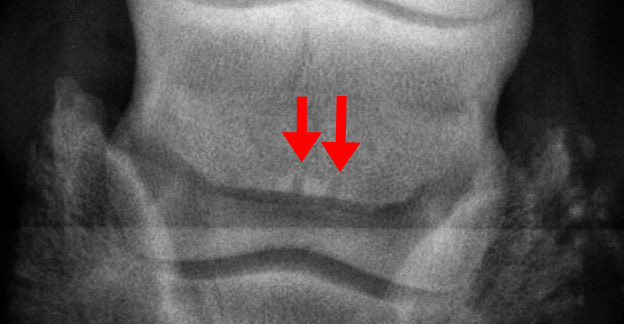

Dies ist das Strahlbein eines Pferdes mit zwei Gefäßkanälen. Die Gefäßkanäle sind deutlich zu sehen, ihre Größe ist eher klein und reicht nicht tief in das Strahlbein, die Kontur der Kanäle ist klar abgegrenzt, es liegt nur eine geringe Zahl vor, die Knochenstruktur des Strahlbeines ist homogen und nicht sklerosiert oder osteolytisch, die obere Kontur des Strahlbeines verläuft gerade und ist unverändert, die Bandansätze sind nicht krankhaft verändert. Die Befunde liegen im Bereich I bis II bzw. Grad 0. Befunde dieser Art sind  nicht krankhaft, sie weichen gering oder gar nicht von der Norm ab, eine Erkrankung ist aus röntgenologischer Sicht nach dieser Aufnahme unwahrscheinlich.